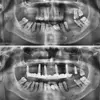

Tooth Loss

Periimplantitis

Peri-Implant Mucositis

Implant Treatment